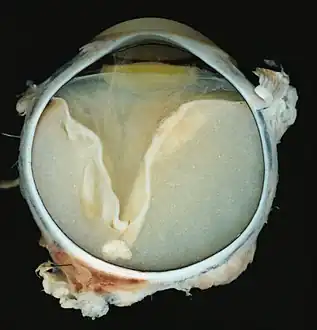

A case of Coats' disease, showing total retinal detachment with subretinal exudate containing cholesterol crystals and a fibrous nodule in the posterior pole -

Grossly, retinal detachment and yellowish subretinal exudate containing cholesterol crystals are commonly seen. Microscopically, the wall of retinal vessels may be thickened in some cases, while in other cases the wall may be thinned with irregular dilatation of the lumen.[10] The subretinal exudate consists of cholesterol crystals, macrophages laden with cholesterol and pigment, erythrocytes, and hemosiderin.[11] A granulomatous reaction, induced by the exudate, may be seen with the retina.[12] Portions of the retina may develop gliosis as a response to injury.